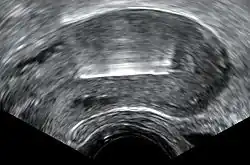

Expulsion rates can range from 2.2% to 11.4% of users from the first year to the 10th year. The TCu 380A may have lower rates of expulsion than other models, and the frameless copper IUD has a similar rate of expulsion to models with frames.[22][23] Expulsion is more likely with immediate or early postpartum or post-abortal placement.[24][25] In the postpartum period, expulsion is less likely when the device is placed less than ten minutes after the placenta is delivered, or when inserted after a cesarean delivery.[16] Unusual vaginal discharge, cramping or pain, spotting between periods, postcoital (after sex) spotting, pain during intercourse (dyspareunia), or the absence or lengthening of the strings can be signs of a possible expulsion.[21] As with intentional removal, the device is immediately ineffective after expulsion. If an IUD with copper is inserted after an expulsion has occurred, the risk of re-expulsion has been estimated in one study to be approximately one third of cases after one year.[26] Magnetic resonance imaging (MRI) may cause dislocation of a copper IUD, and it is therefore recommended to check the location of the IUD both before and after MRI.[27]

Perforation of the device through the uterine wall typically occurs at the time of placement, though it may occur spontaneously during the period of use. Estimates of the rate of perforation vary from 1.1 per 1000 to 1 per 3000 copper IUD insertions.[1][11] Perforation may be slightly more common in people using the copper IUD while breastfeeding.[28]